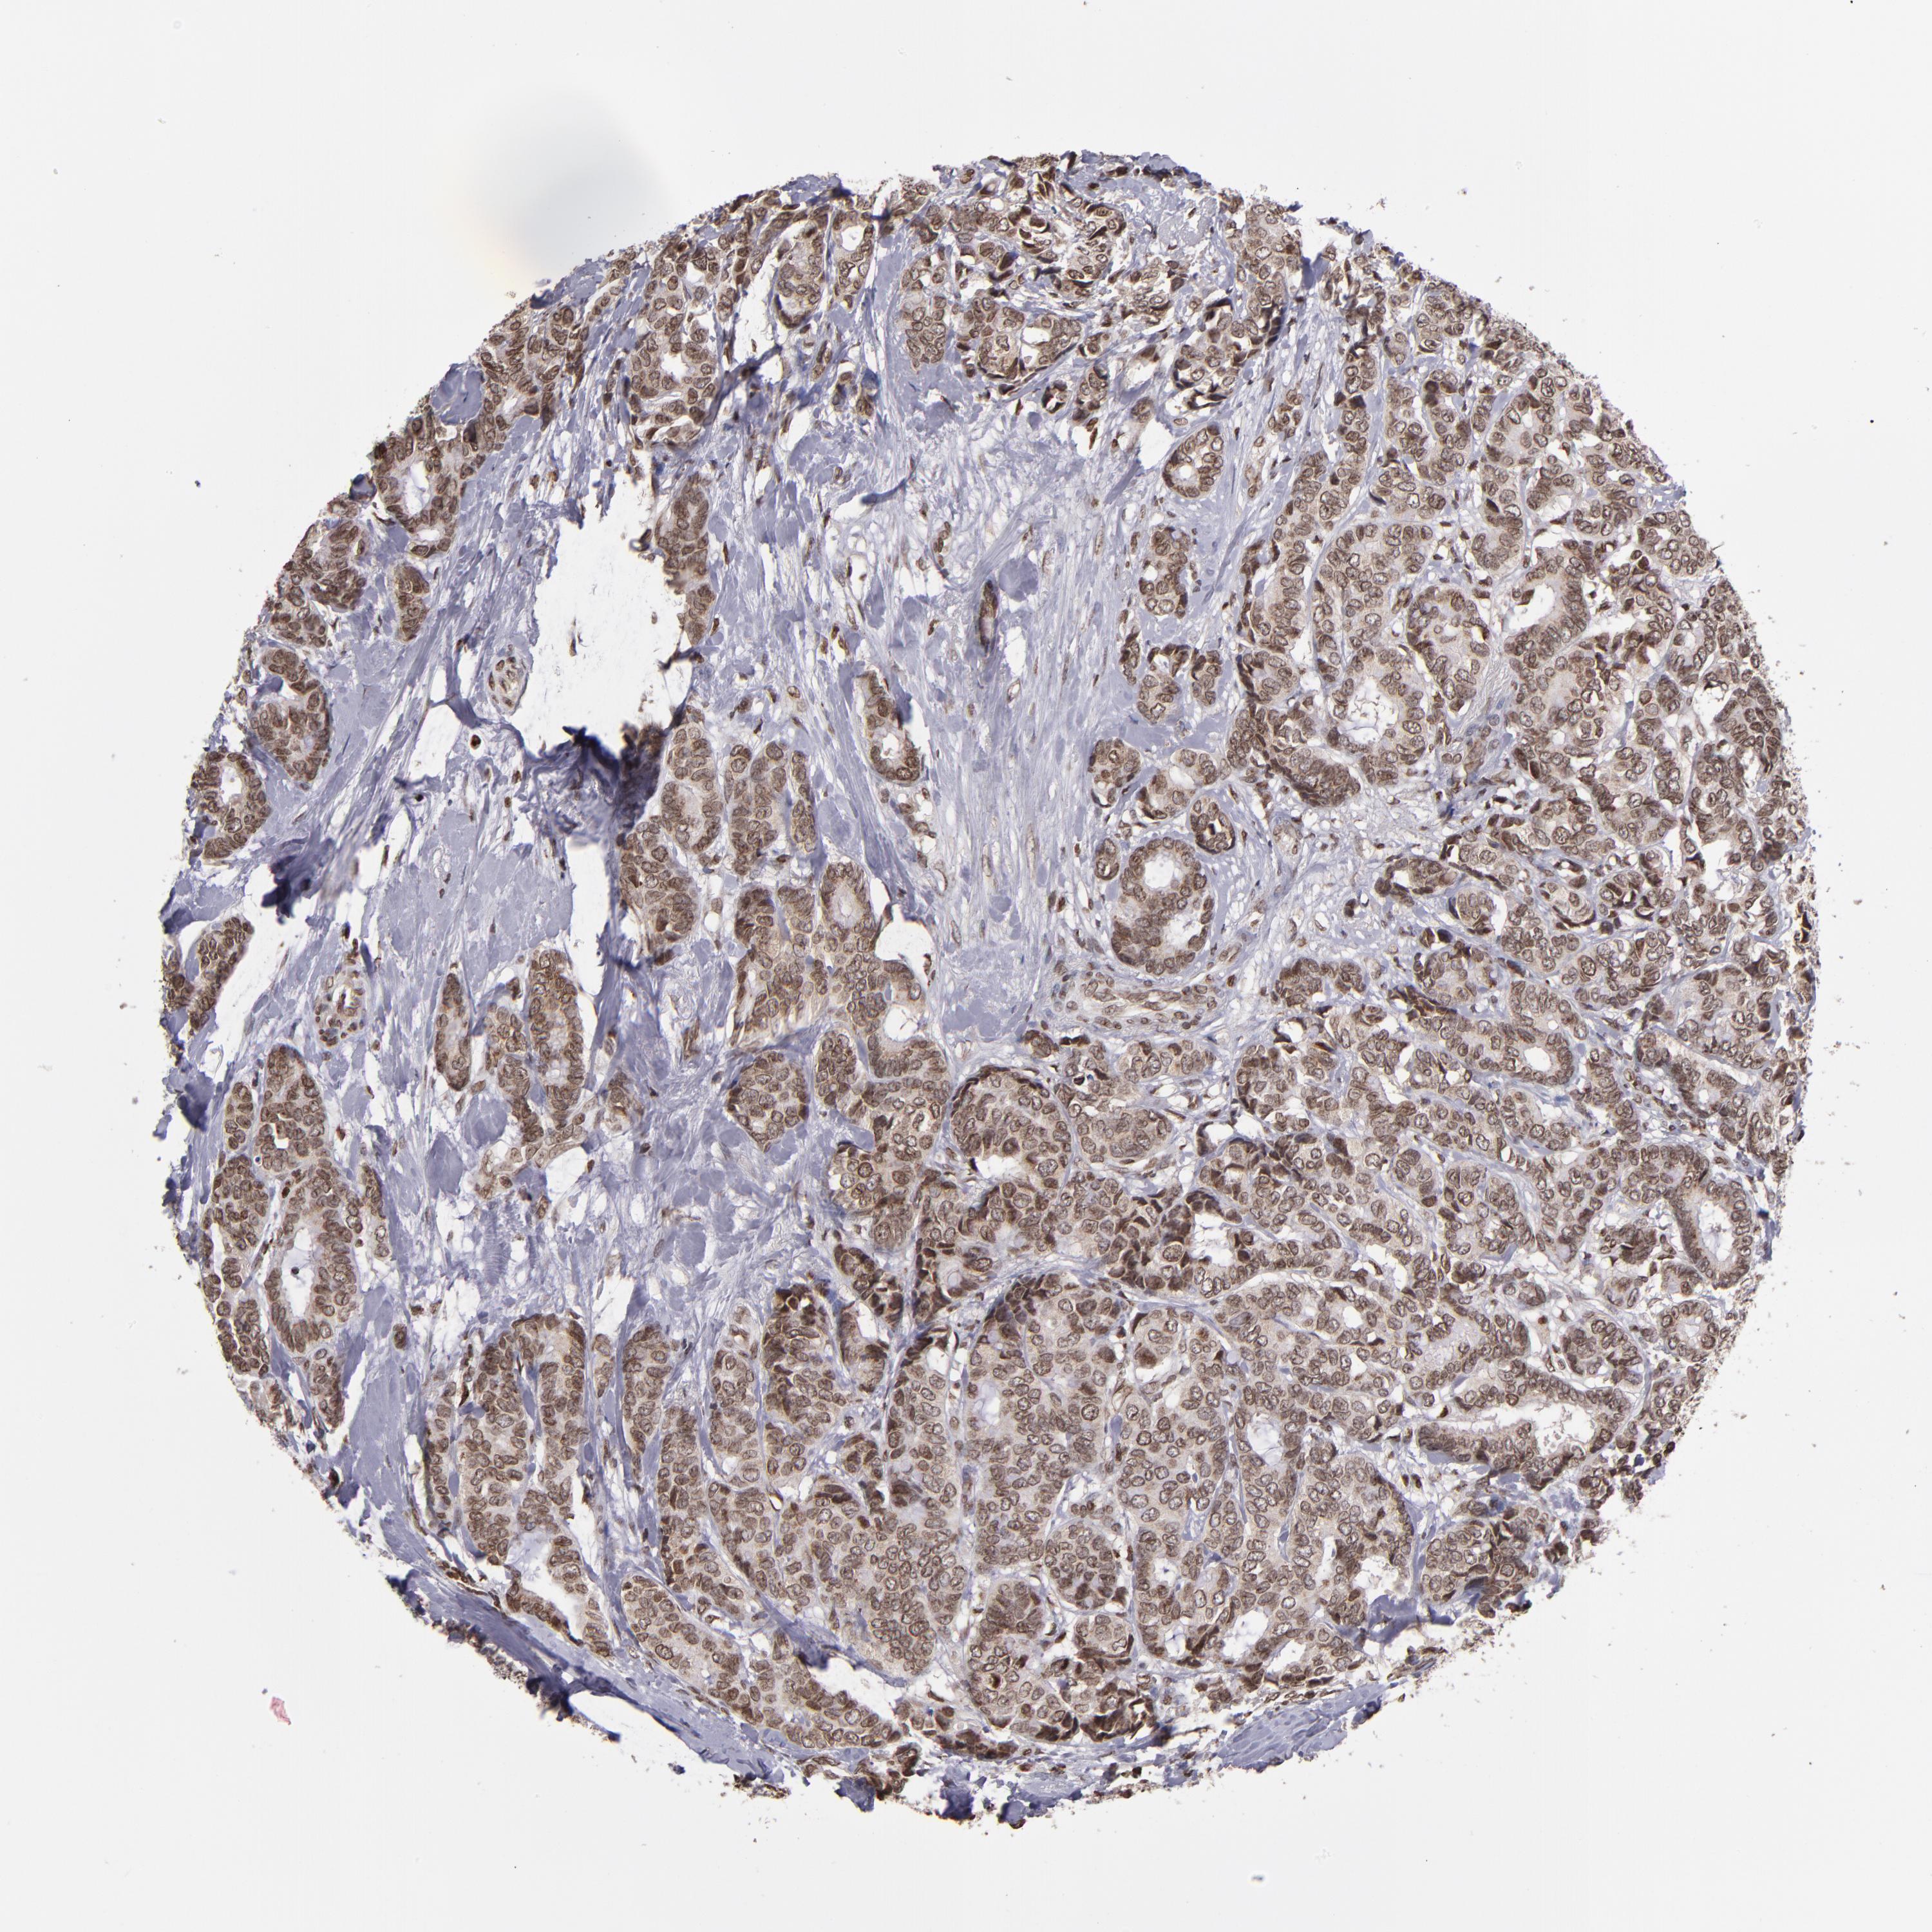

CANCER BREAST CANCER Show tissue menu

BRCA TCGA BRCA VALIDATION PROTEIN EXPRESSION

ANTIBODIES

AND

VALIDATION